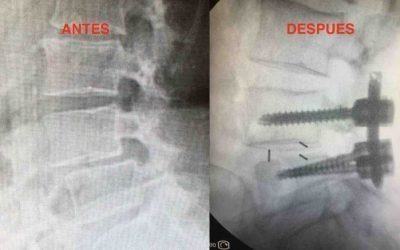

Artrodesis lumbar percutánea

La artrodesis lumbar, es decir la fijación de dos o más vértebras sigue siendo la cirugía que más se realiza en la columna. Ya sea cirugía abierta o...

Artrodesis percutánea

El dolor de la columna vertebral cervical o cervicalgia es una causa común de consulta médica, en este articulo hablaré sobre el tratamiento quirúrgico de la...